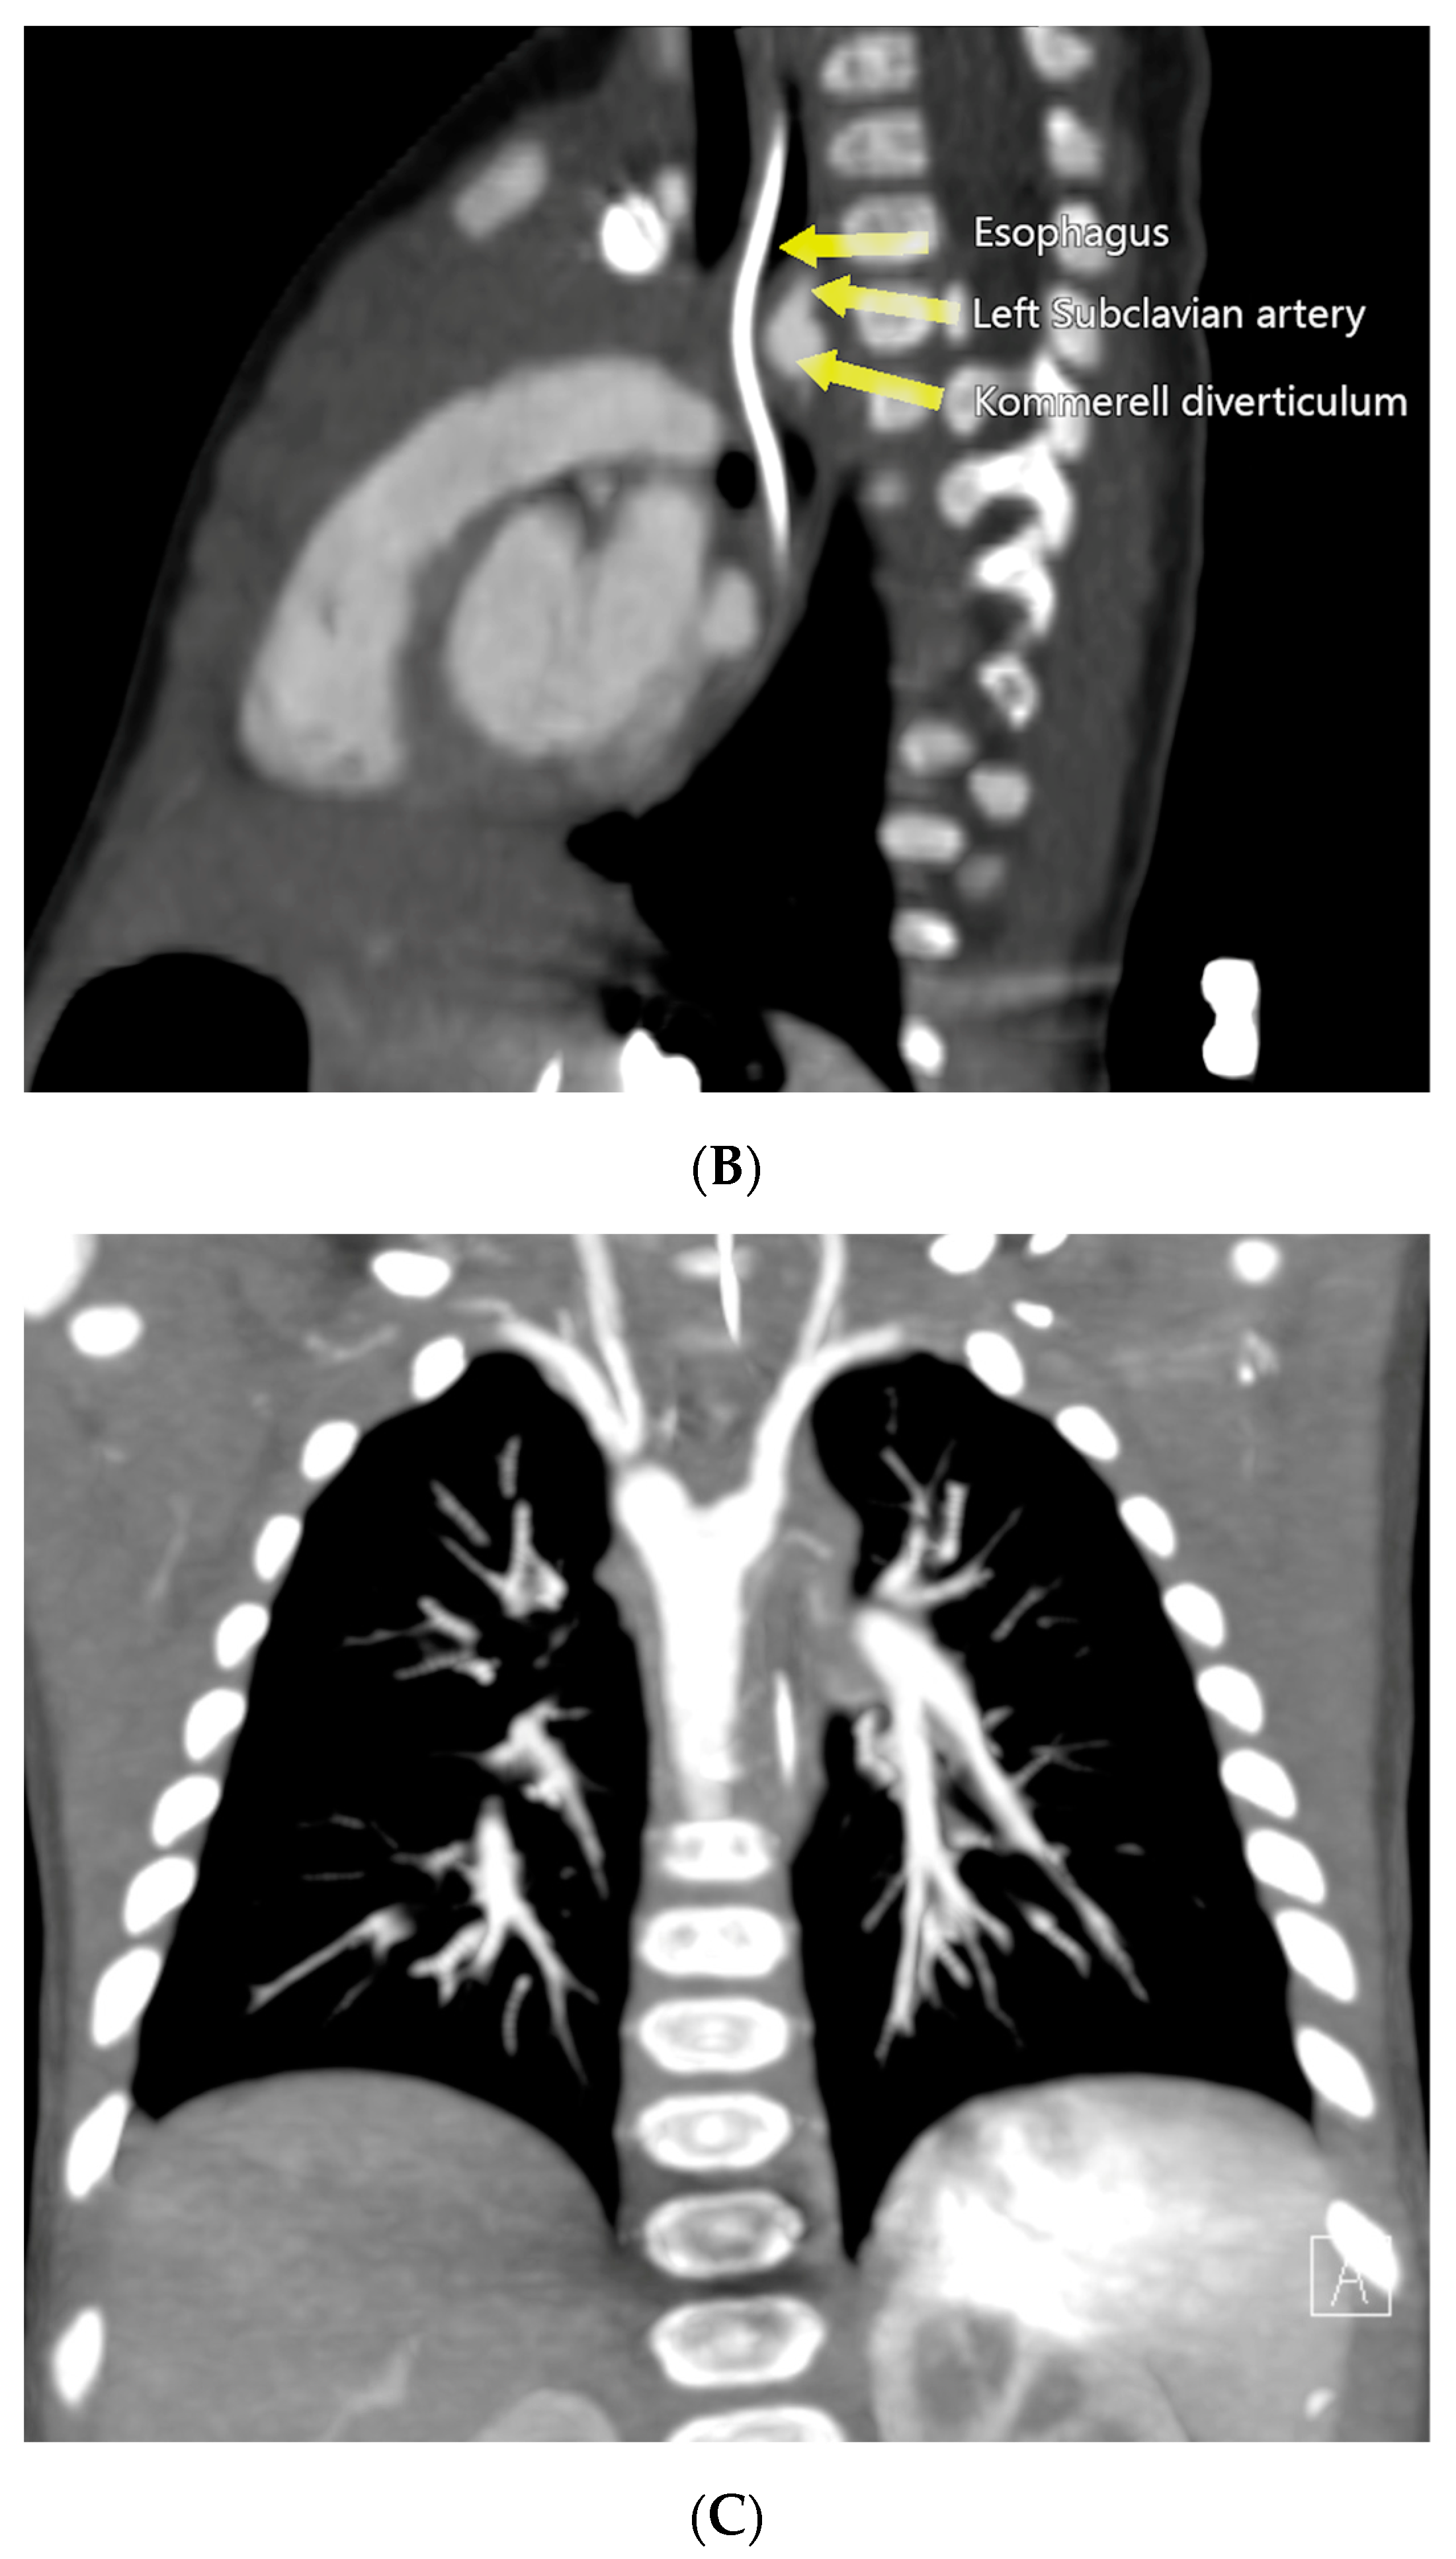

This finding prompted a Computed Tomography Angiography (CTA), which revealed a vascular ring formed by a right aortic arch (RAA), an aberrant left subclavian artery (LSA) originating from an aneurysmal dilation at its base, the so-called Kommerell’s diverticulum (KD), and a left ligamentum arteriosum (LLA) (Figure 2) (Supplementary Material Video S1).

Figure 2.

Preoperative Computed Tomography Angiography. (A) Three-dimensional reconstruction of an RAA with the LCA as the first branch and the retroesophageal aberrant LSA as the fourth branch, originating from a KD. (B) Sagittal view demonstrating esophageal narrowing and the presence of a nasogastric tube. (C) Coronal view showing the aneurysmal dilation of the base of the LSA.